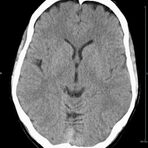

Kopf

• Schlaganfalldiagnostik

• Traumadiagnostik (Akutdiagnostik nach Verletzungen, Unfällen)

• Nasennebenhöhlen (Entzündungen, Tumore)